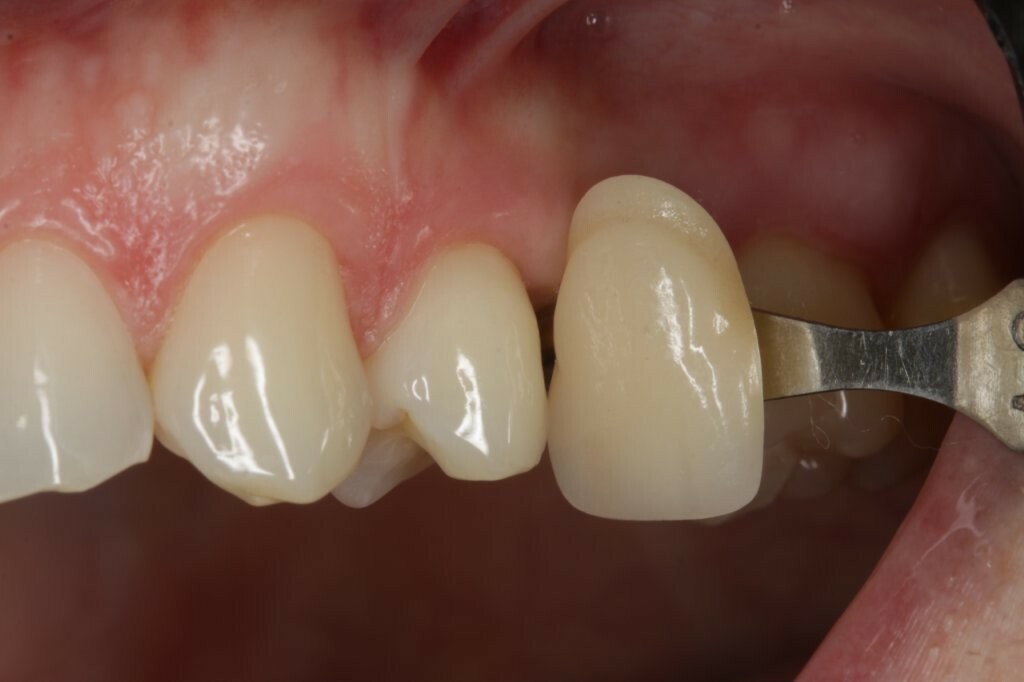

Zu Beginn wurde das Einzelzahnimplantat (Conelog ScrewLine Titanimplantat, 3,8 x 9,0 mm, Camlog) in Regio 25 gesetzt, geschlossen eingeheilt und nach Freilegung mit einem Gingivaformer (Conelog Gingivaformer, wide body, 3,8 x 6,0 mm, Camlog) versehen (Abb. 3). Mithilfe eines VITA-Farbschlüssels (VITA Zahnfabrik) wurde für die spätere Krone die Farbe A3 bestimmt (Abb. 4).